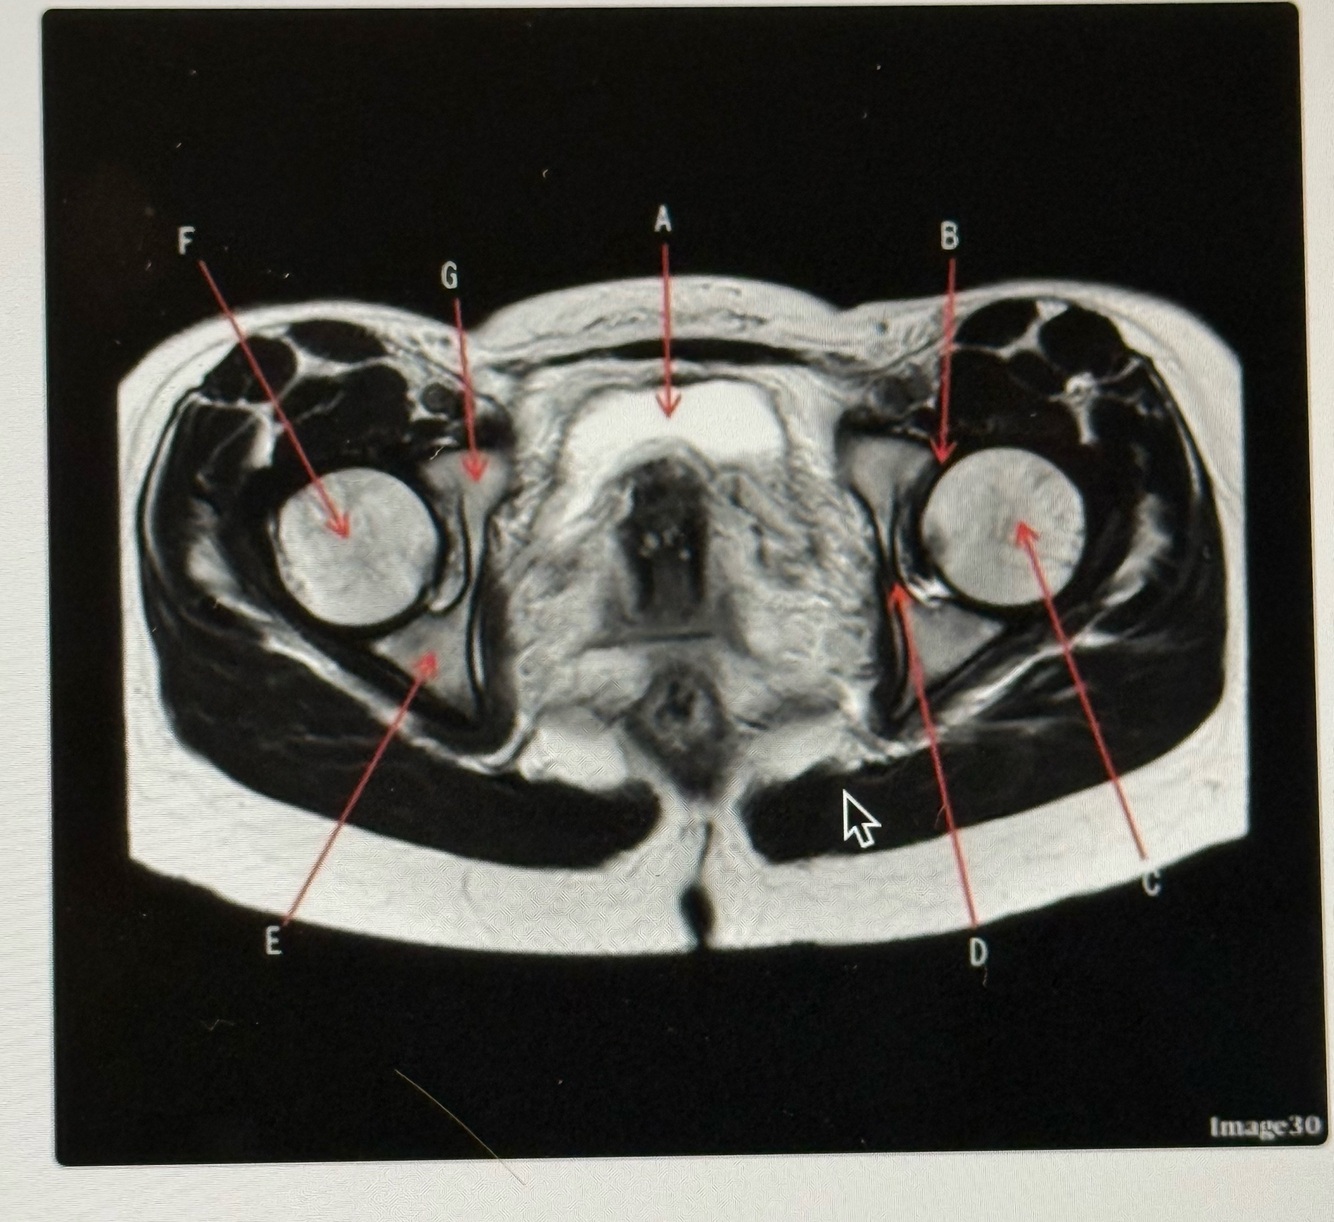

The image below is a ______ weighted image acquired in the _____ scan plane.

A

T2; Axial

Q

Letter A is pointing to the

Bladder

6

Letter B is pointing to the